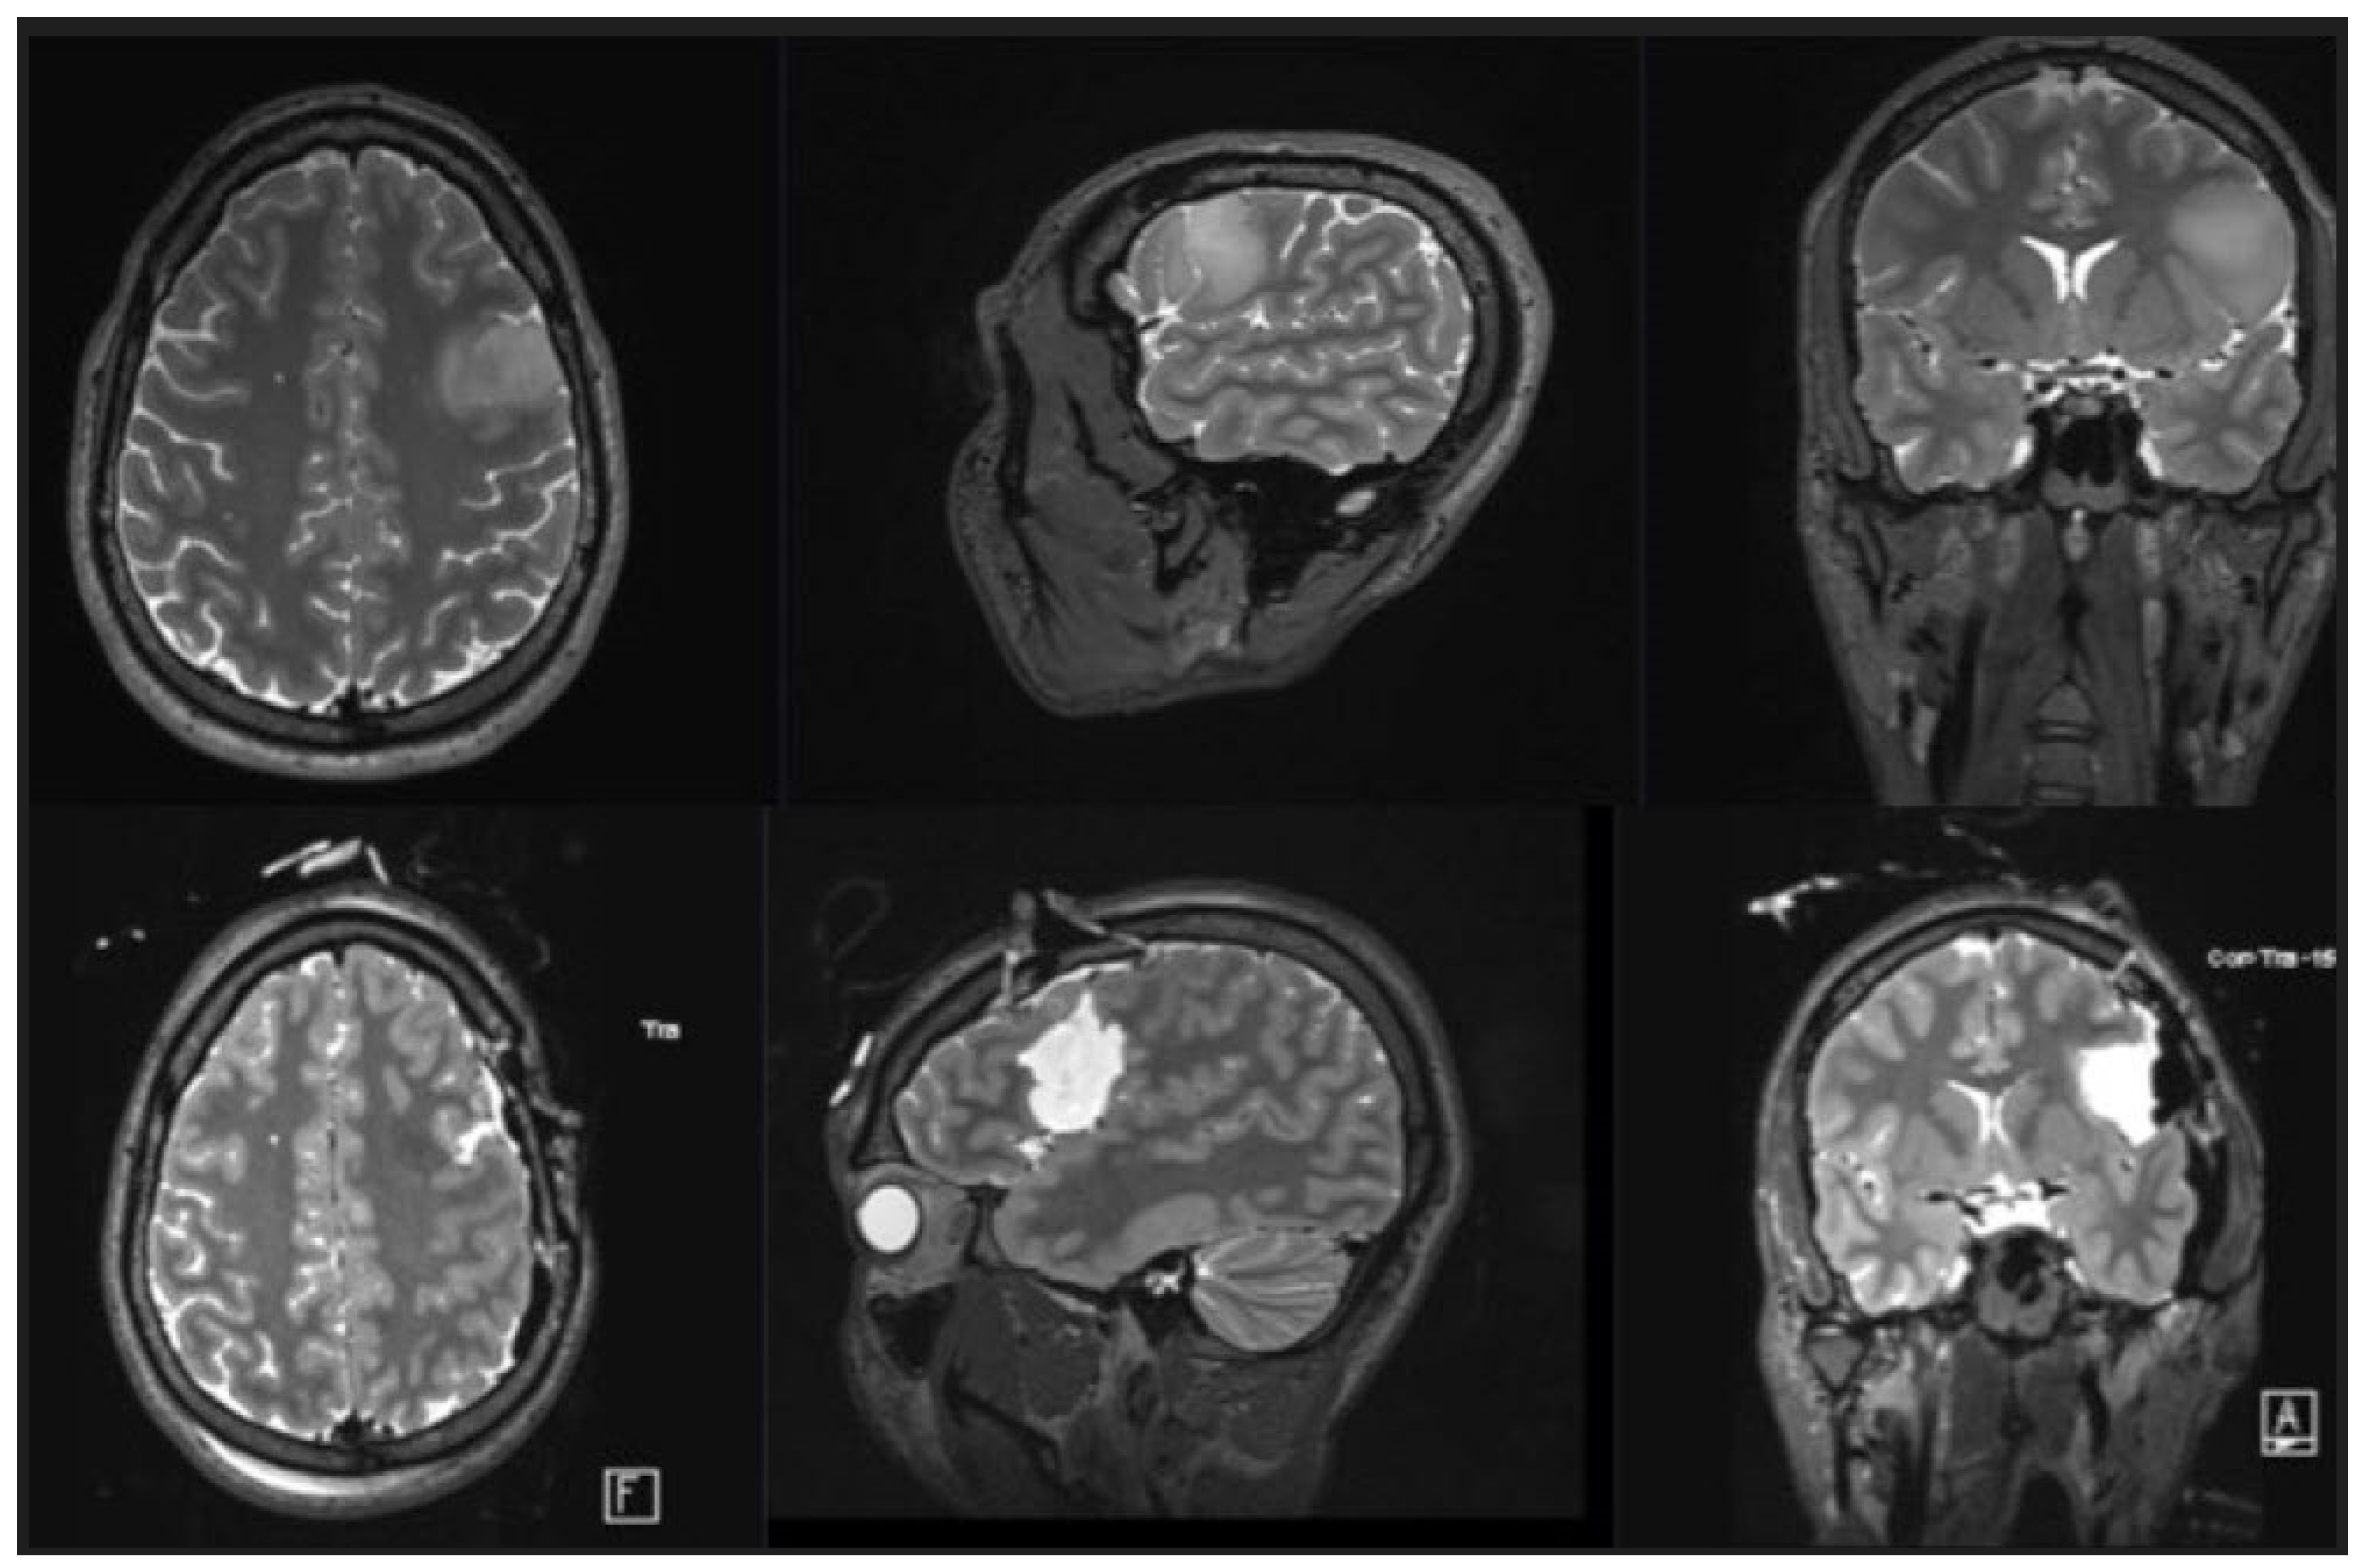

3.1. Patient Population

3.2. Intraoperative Findings

3.3. Clinical Findings